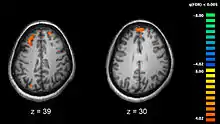

_-_ara.png.webp)

يرتبط الفصام باختلافات دقيقة في بُنيان الدماغ، وُجدت لدى 40 إلى 50% من الحالات، وفي كيمياء الدماغ أثناء الحالات الذهانية الحادة.[10] وقد أظهرت الدراسات التي تستخدم الاختبارات العصبية والتصوير العصبي مثل التصوير بالرنين المغناطيسي الوظيفي والتصوير المقطعي بالإصدار البوزيتروني لفحص الاختلافات الوظيفية في نشاط الدماغ بأن هذه الاختلافات تحدث غالبًا في الفص الجبهي وقرن آمون والفص الصدغي.[68] وقد تم الإبلاغ عن وجود انكماشات في حجم الدماغ أصغر من تلك التي وُجِدت في مرض الزهايمر في مناطق من القشرة الأمامية والفصوص الخلفية. ومن غير المؤكد ما إذا كانت تلك التغييرات في الحجم آخذه في التقدم أم أنها كانت مسبقة الوجود قبل بداية المرض.[31] وقد تم ربط تلك الاختلافات بعجز الإدراك العصبي والذي غالباً ما يرتبط بالفصام.[69] نظرا لتغير الدارات العصبية، فقد اقتُرح أن يُنظر إلى الفصام وكأنه مجموعة من اضطرابات التطور العصبي.[70] هناك بعض النقاشات حول إذا ما كان العلاج بمضادات الذهان ذاته يسبب انكماشات في حجم الدماغ.[71]